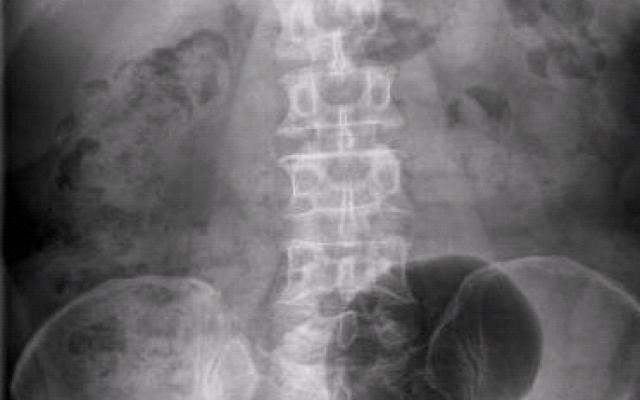

Dit artikel is alleen beschikbaar als PDF.Lees de PDF Artikelinformatie Online verschenen op 28 januari 1959 Citeer dit artikel als Ned Tijdschr Geneeskd. 1959;103:407-10 Heb je nog vragen na het lezen van dit artikel? Check onze AI-tool en verbaas je over de antwoorden. ASK NTVG Ook interessant Beeldquiz Een man met chronische buikpijn en obstipatie Nieuws Chronische functionele obstipatie bij kinderen Nieuws Chronische obstipatie en koemelkallergie bij kinderen Meer gerelateerd … Reacties Login om een reactie te plaatsen